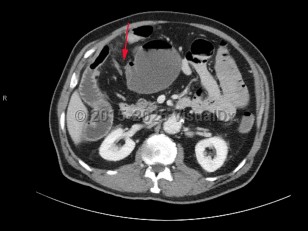

- Obtain urgent surgical consultation and administer early antibiotics for patients presenting with signs of bowel ischemia or sepsis.

- Give fluid resuscitation to patients presenting with hypovolemia or signs of shock, with pressors as needed.

- Provide symptomatic therapy with intravenous (IV) pain medication and antiemetics.

- Give the patient nothing by mouth.

- Gastric decompression with a nasogastric tube (NGT) is not recommended in all cases but may assist in patients with severe abdominal distension.